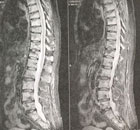

IRM ou NON ?

Dr Jacques Fechtenbaum Hôpital Cochin - Paris

Mme P., 70 ans, est suivie depuis 4 ans pour un cancer du sein et traitée par anti-aromatase.

Elle a présenté des rachialgies diffuses lors d’un déménagement, d’horaire mixte.

La radiographie standard a montré 4 fractures vertébrales (FV) : T7, T9, T11 et T12, sans aucune caractéristique particulière, ni suspicion de lésions secondaires.

Cependant, devant l’horaire, le nombre de FV et le terrain, une IRM a été demandée.